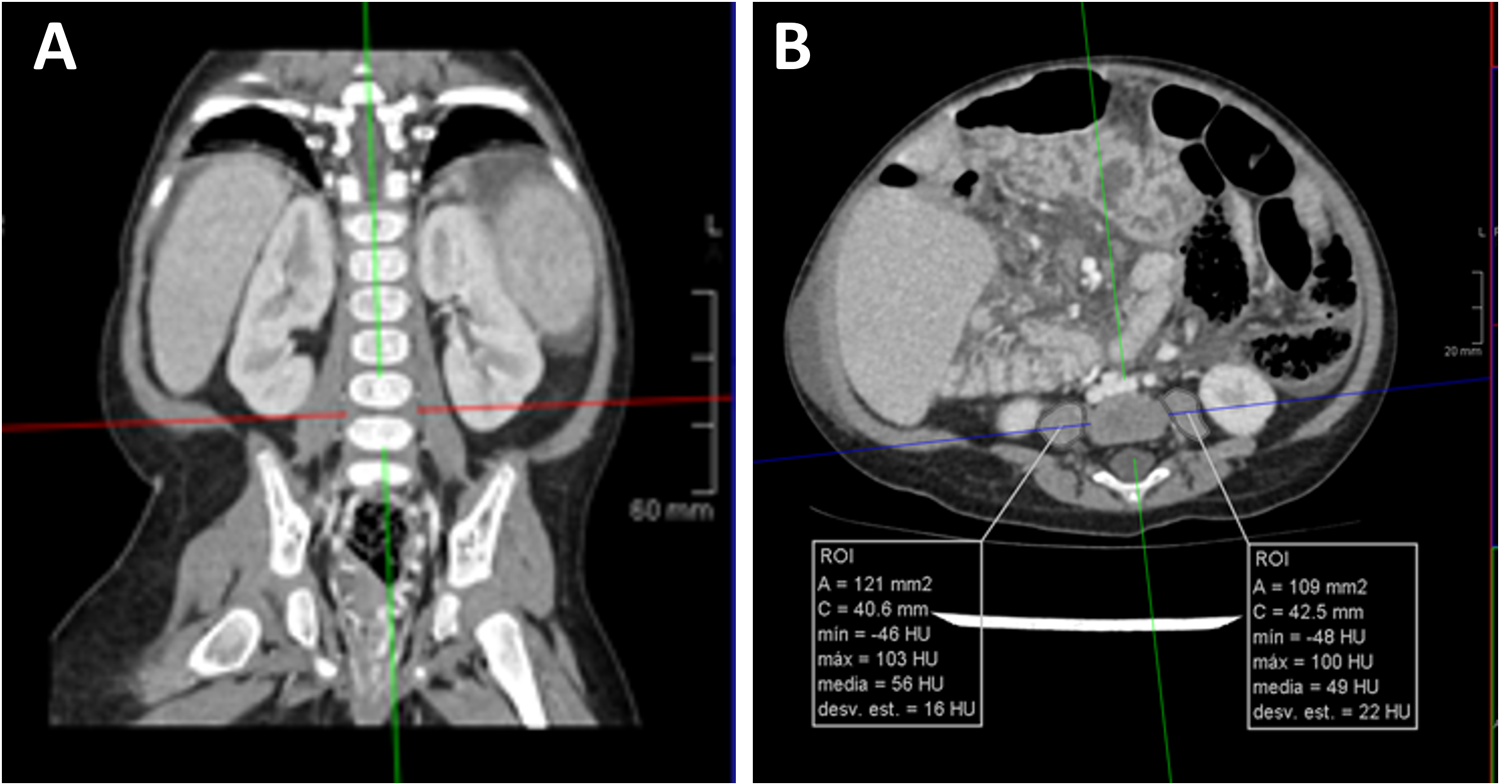

Abdominal CT images were reviewed by one expert in pediatric radiology (M.P.). From axial CT images, L4–5 level was identified following cross-referencing on sagittal and coronal plane reconstruction. On axial cross-sectional CT images, cross-sectional area of the psoas muscle was measured using a dedicated free-hand drawing tool at 2 separate intervertebral lumbar disks (L4–5) level by PACS software (IMPAX Volume Viewing 4.0. Agfa HealthCare Clinical applications, Mortsel, Belgium).

Total psoas surface muscle area (tPMA), was expressed as the sum of the right and left PMA in square millimeters (mm2) at the same level (24, 25). We performed one measurement at L4–5 level, it has been shown to be the most clinical relevant and useful measure in children (25) (Figure 1). It was divided by height squared and expressed as psoas muscle index (PMI, mm2/m2). As there are no validated cut-off points for infants as to accurately define sarcopenia, we used PMI as a continuous variable in this study (25).

Figure 1

Measurement of psoas muscle mass in CT scan. Panel (A). From axial CT images, L4-5 level was identified following cross-referencing on sagittal and coronal plane reconstruction (red line in left image). Panel (B). On axial cross-sectional CT images, cross-sectional area of the psoas muscle (white lines in right image) was measured using a dedicated free-hand drawing tool.